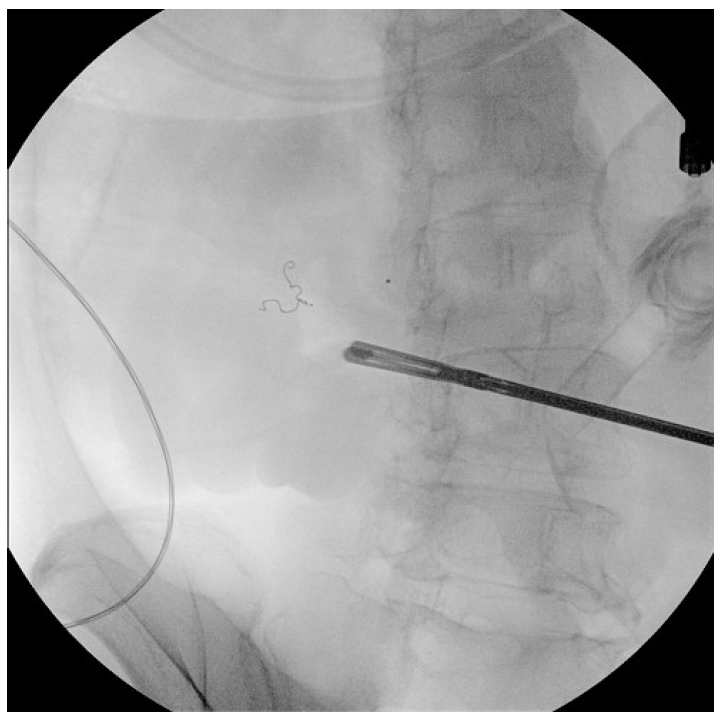

수술 중 병변의 위치를 찾기 위하여 병변으로 의심되는 부위에 클립을 결찰한 후 코일과의 상대적인 위치를 C-arm을 통해 확인하여 보정하는 과정을 거쳤다. 회결장동맥(ileocolic vessel)을 결찰한 뒤 장간막동맥(mesenteric branch)에 위치한 코일이 확인되었고(Fig. 4) C-arm을 통해 코일의 위치를 재확인하여 병변의 위치를 특정하였다. 리가슈어(LigaSureTM; Medtronic, Minneapolis, MN, USA)로 장간막을 나눈 후 장간막 반대편 경계를 따라 말단 회장 근처의 소장 절제술을 시행하였다(Fig. 5A). 절제된 소장 부위에서 궤양성 병변이 확인되어 소장을 봉합한 후 수술을 마무리하였다.

Figure 5.

(A) Red arrows indicate a resected specimen of the ileum with a single, round ulcerative lesion on the antimesenteric aspect. (B) Red arrows indicate hyperplastic lymphoid follicles within the subepithelial layer (hematoxylin and eosin stain, × 40). At the bleeding site, mucosal erosion was microscopically confirmed, and the erosive surface exposed ecstatic capillaries.

총 15.8 cm의 소장이 절제되었고 병리조직 육안 검사상 2.2 × 2.0 cm 크기의 궤양이 관찰되었으며 조직 검사상 결절성 림프구양 증식증(nodular lymphoid hyperplasia)으로 진단되었다(Fig. 5B). 이후 추가적인 혈변 없이 혈색소 수치 안정화 후 항혈소판제를 재시작하였다. 환자는 현재 안정적으로 기저질환에 대하여 추적 관찰 중이다.